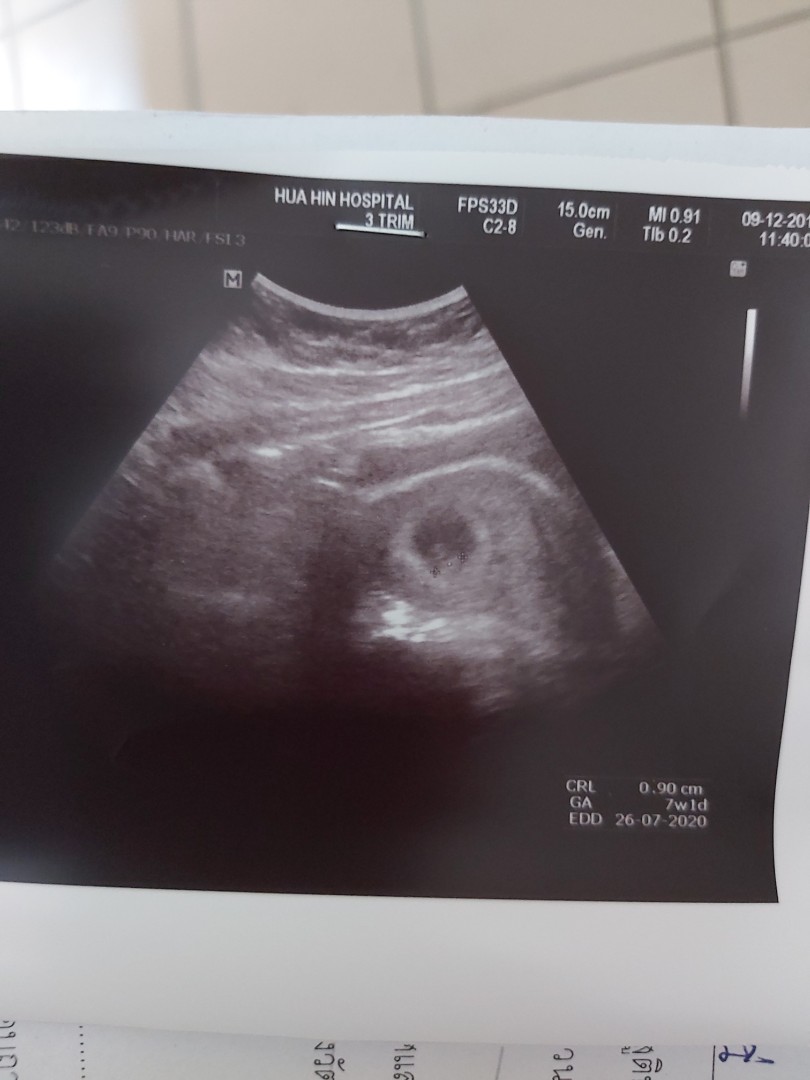

7สัปดาห์จ้า